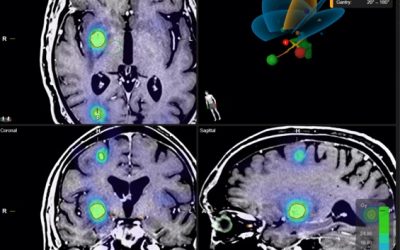

La radiocirugía craneal (SRS) y extracraneal (SBRT) dos aliadas a vuestro lado

¿Alguna vez has imaginado que un rayo atraviesa tu cuerpo de forma casi imperceptible y es capaz de atacar con suma precisión tus metástasis eliminando su actividad e incluso haciéndolas...